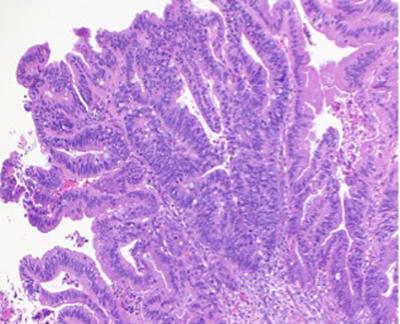

Histopathologic examination showed fragmented specimen containing adenocarcinoma, characterized by relatively well formed glands with cribriform glands in some areas. The epithelial cells were relatively uniform with basally oriented nuclei and intracytoplasmic mucin was present in a subset of cells. Some areas contained areas of necrotic cellular debris within the lumens of the neoplastic glands. No areas of non-atypical endometrial hyperplasia or endometrial intraepithelial neoplasia were identified. There were fragments of leiomyomas in the background. Immunohistochemical analysis demonstrated the adenocarcinoma cells to be positive for CK20, CDX-2, SATB-2 (patchy), MUC2 (patchy) and CEA. They were negative for CK7, PAX-8, GATA-3, ER, PR, Vimentin and hrHPV in-situ. The p16 and MUC6 showed rare positive neoplastic cells, and p53 demonstrated a wild type pattern. Mismatch repair proteins were intact. The combined morphologic and immunohistochemical features support and adenocarcinoma with an enteric/gastrointestinal phenotype. The case was finalized as moderately differentiated adenocarcinoma with intestinal/enteric phenotype. In the absence of any notable conventional endometrioid adenocarcinoma or precursor endometrial proliferation, the differential diagnosis included a metastasis (likely from colorectal origin or other sites which may acquire an intestinal phenotype, and an unusual primary endometrial carcinoma with pure intestinal metaplasia/differentiation. Additional workup to exclude extrauterine primary sites was recommended.

Fig. 1 Adenocarcinoma embedded in endometrial stroma (A and B). Adenocarcinoma with dirty necrosis (C) and intracytoplasmic mucin (D). The malignant cells are negative for CK-7 (E) and positive for CK-20 (F), CDX-2 (G), SATB-2 (H).